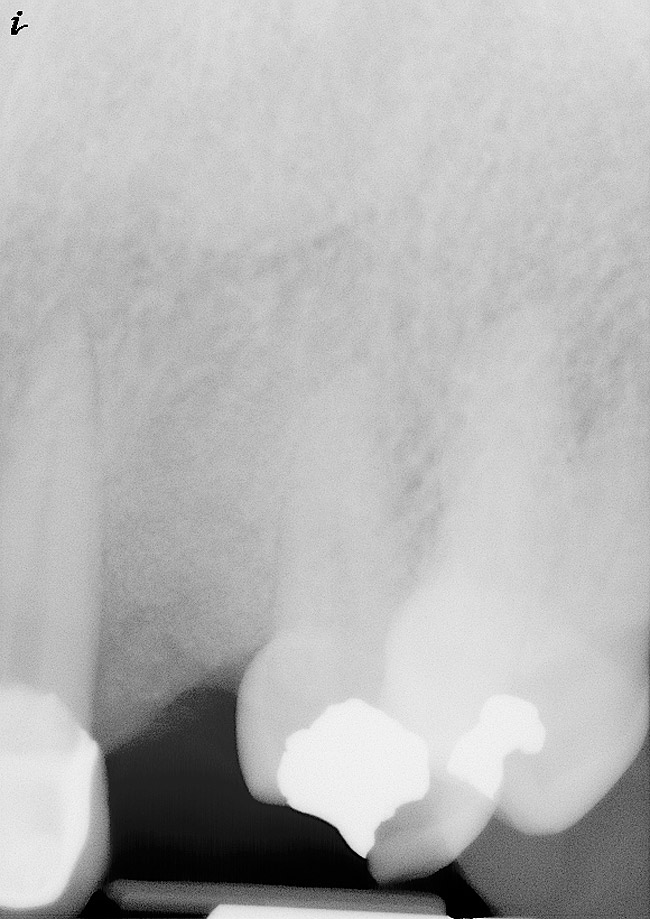

In the present case, a submarginal incision was made at the mucogingival gingival junction, revealing the facial fenestration defect (Figure 10 ). The mucosa was elevated to access and graft both the socket and fenestration defect. Both sites were protected by a collagen membrane (Bio-Gide®), and sutured to close the submarginal incision (Figure 11 ). Medical cyanoacrylate was placed over the socket wound to stabilize the collagen membrane. Healing was uneventful, and the soft-tissue contours suggested preservation of the alveolar contours at the time of extraction. Five months after extraction and augmentation, the findings from a clinical postoperative radiograph demonstrated evidence of notable graft containment as reflected by the overall radiopacity of the extraction site, even coronal to the socket. The site was reentered for implant placement. Flap elevation revealed the dense bone ridge with complete incorporation of the particulate graft material. The osteotomy for implant placement was prepared with a trephine bur, and the resulting specimen was submitted for histologic evaluation. The histologic findings revealed evidence of robust osteogenesis throughout the bone core, including the coronal aspect supporting the soft tissue. New bone was found in close amalgamation with the FDBA-graft particles throughout the specimen. A dental implant was placed at the site in a single-stage surgery and allowed to heal for 5 months prior to the restoration. The esthetic outcome was highly acceptable, with preservation of the marginal and papillary gingiva contours (Figure 12 ). The radiographic findings showed consistent normal bone remodeling and implant integration (Figure 13 ).

Figure 13  Postoperative findings were consistent with normal bone remodeling and implant integration.

Figure 13

Figure 15& Radiographic findings consistent with complete bone fill of the defect at 5 months post-treatment.

Figure 15